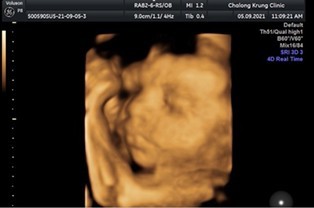

ทีมพฤศจิกายน 29w+5d👶

ผมมีจู๋ครับ💕 ลูกชายคนแรก น้องกลับหัวแล้ว😊 แม่ๆทีมพฤศจิกายนกี่วีคกันแล้วคะได้ลูกสาวหรือชายกันคะ☺☺☺